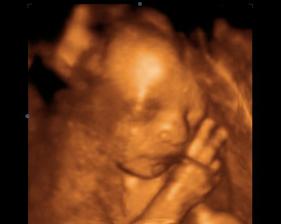

Baby 🙂

Tak uz som tu, narodil som sa 23.2.2008, s mierami 2800g a 48 cm, bol som malicky, ale vsetko dobehnem.